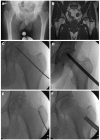

Osteonecrosis is a phenomenon involving disruption to the vascular supply to the femoral head, resulting in articular surface collapse and eventual osteoarthritis. Although alcoholism, steroid use, and hip trauma remain the most common causes, several other etiologies for osteonecrosis have been identified. Basic science research utilizing animal models and stem cell applications continue to further elucidate the pathophysiology of osteonecrosis and promise novel treatment options in the future. Clinical studies evaluating modern joint-sparing procedures have demonstrated significant improvements in outcomes, but hip arthroplasty is still the most common procedure performed in these affected younger adults. Further advances in joint-preserving procedures are required and will be widely studied in the coming decade.